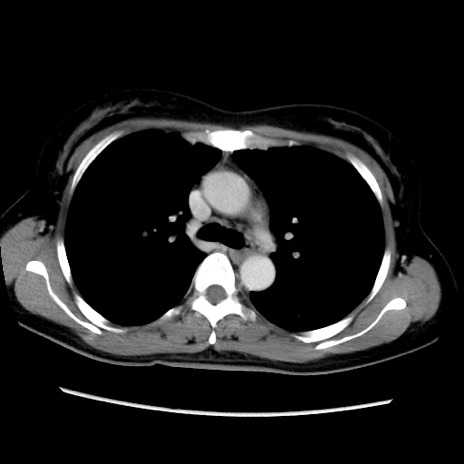

症例39(横断像)

【症例】40歳代女性

【主訴】上下腹部痛

【現病歴】2日目から下腹部痛あり。夜間は痛みで眠れなかった。昨日より上腹部痛と下痢が出現。臥位で痛みは軽快したため、休んでいた。本日になって臥位でも立位でも痛みが強くなってきたため救急要請。

【既往歴】子宮内膜症

【身体所見】部:平坦・軟、左上下腹部に圧痛あり、反跳痛あり。

【データ】WBC 21800、CRP 26.78